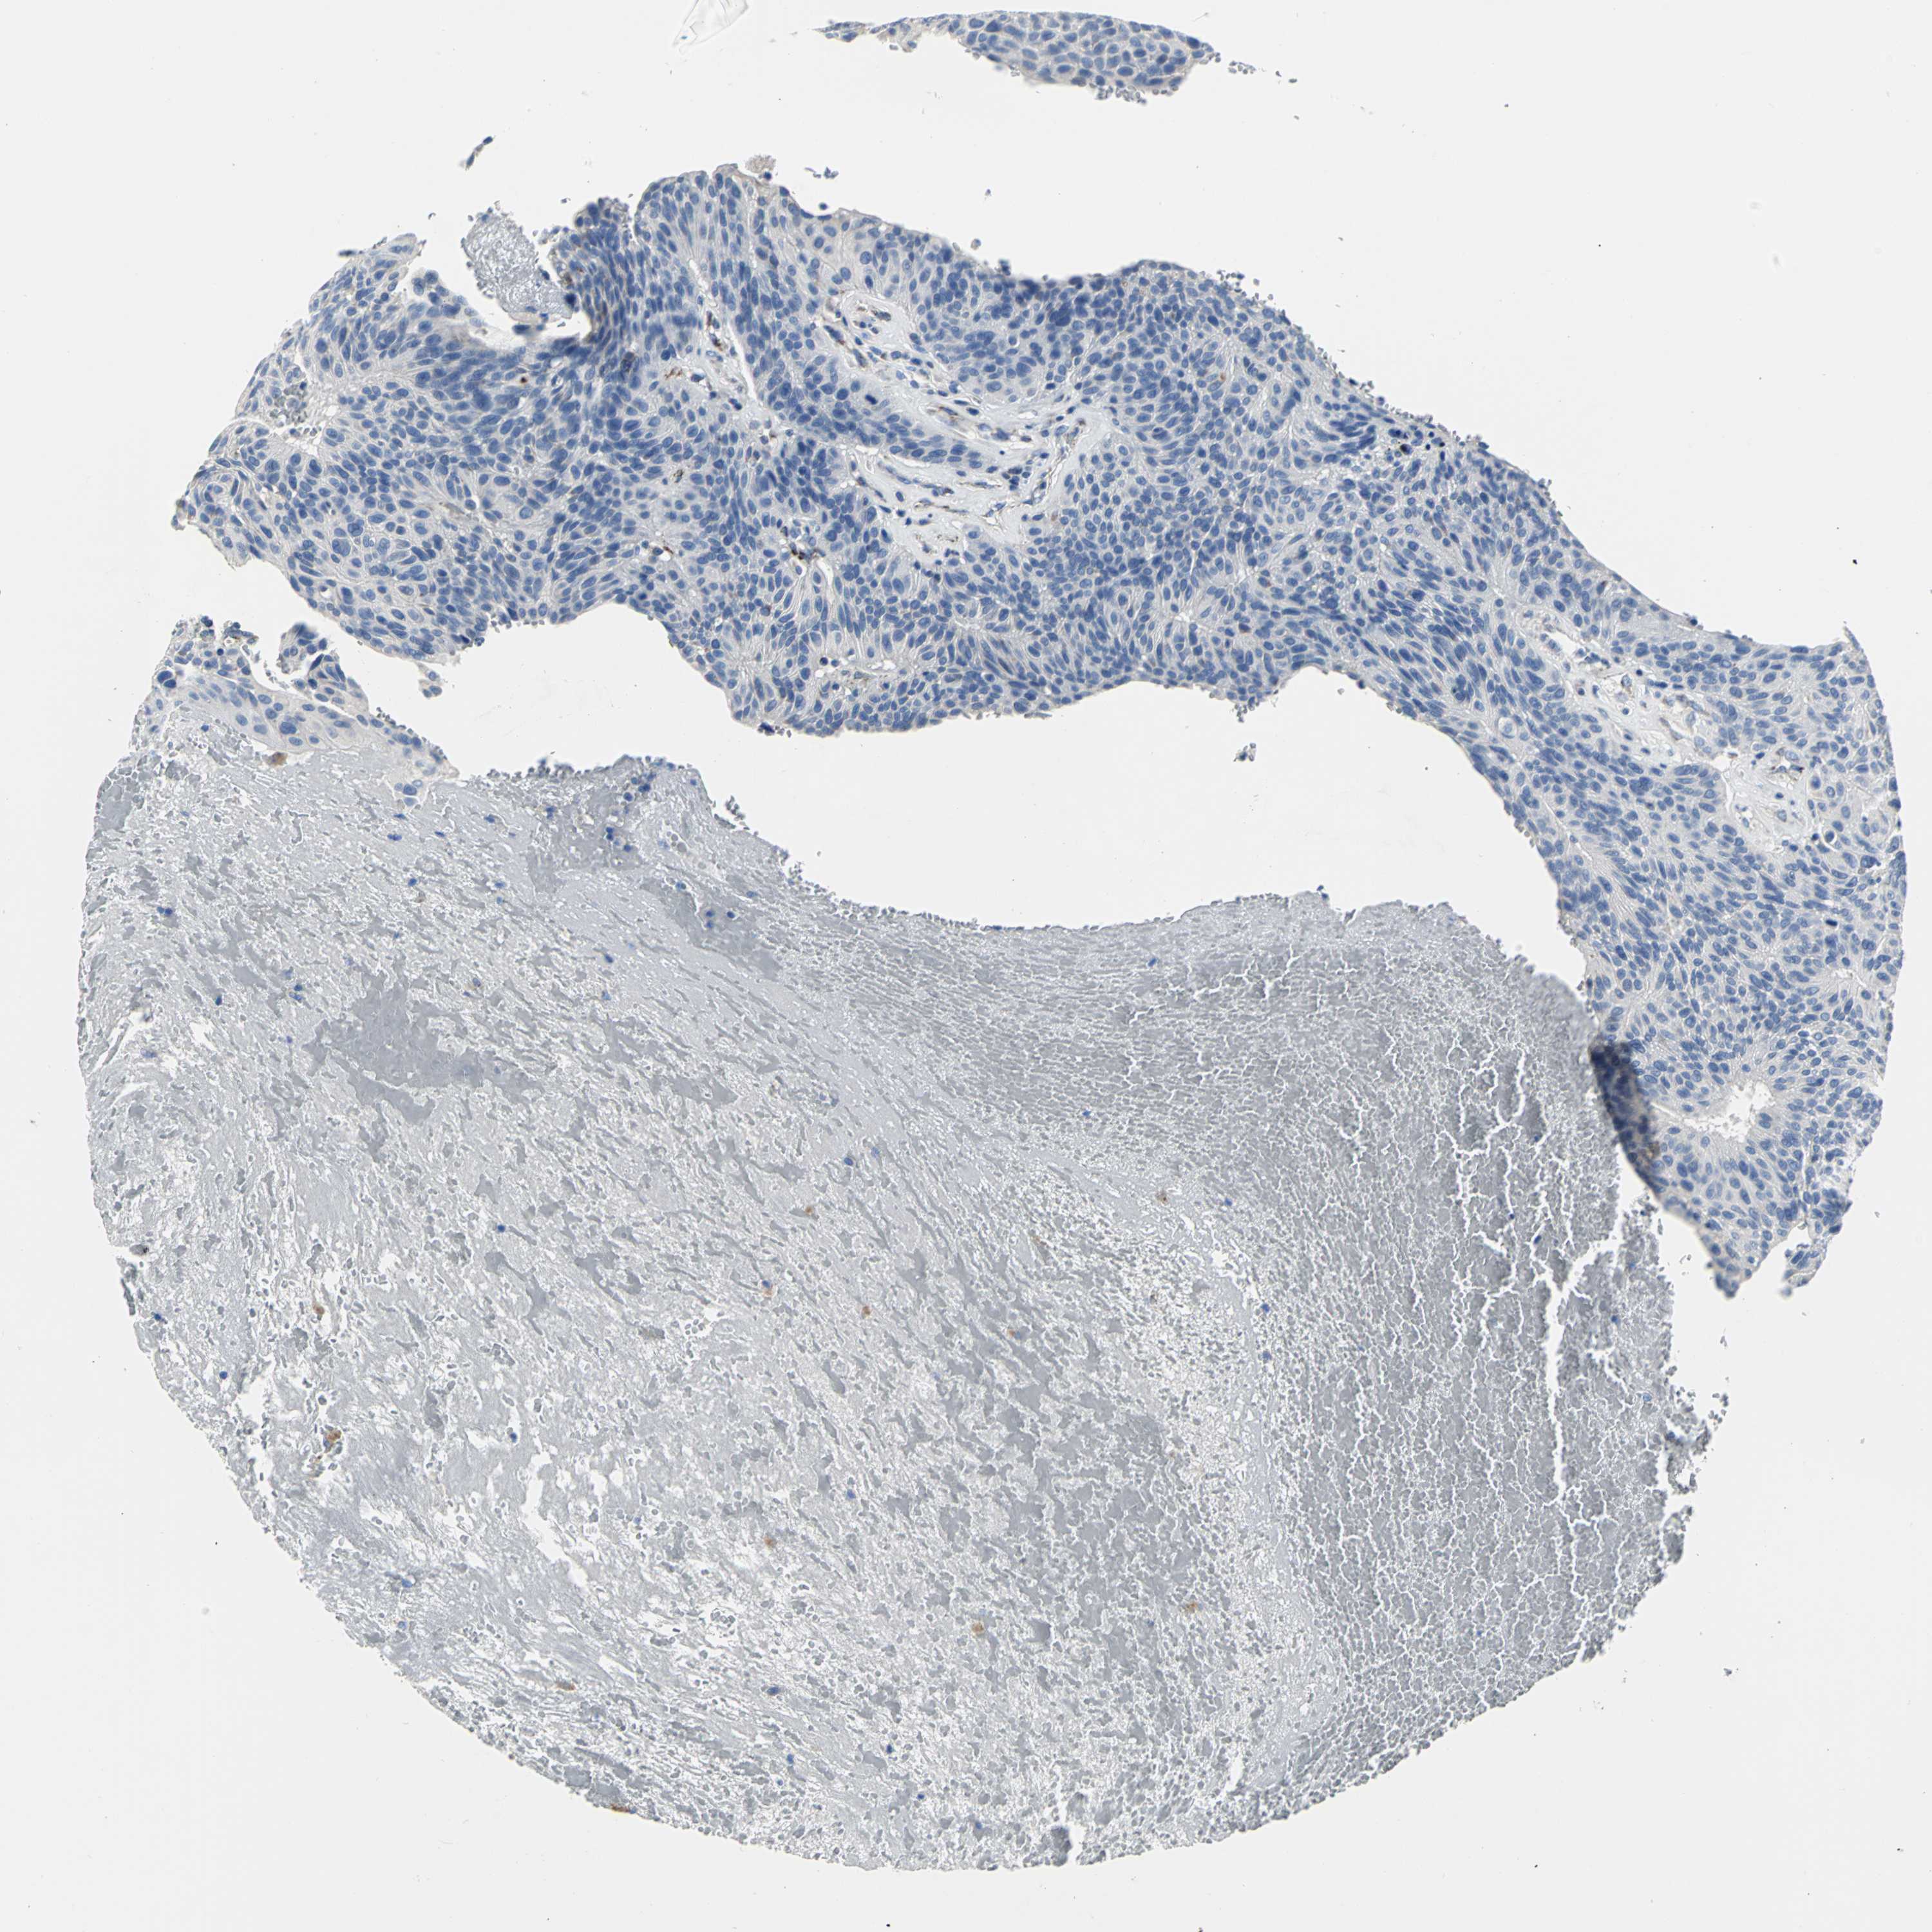

UROTHELIAL CANCER - Protein expressioni

A mouse-over function shows sample information and annotation data. Click on an image to view it in a full screen mode. Samples can be filtered based on level of antibody staining by selecting one or several of the following categories: high, medium, low and not detected. The assay and annotation is described here.

Note that samples used for immunohistochemistry by the Human Protein Atlas do not correspond to samples in the TCGA dataset.

Antibody stainingi

Antibody staining in the annotated cell types in the current human tissue is reported as not detected, low, medium, or high, based on conventional immunohistochemistry profiling in selected tissues. This score is based on the combination of the staining intensity and fraction of stained cells.

Each image is clickable and will lead to virtual microscopy that enables deeper exploration of all samples and also displays staining intensity scores, fraction scores and subcellular localization as well as patient and tissue information for each sample.

Antibody HPA005543

Staining

High

Medium

Low

Not detected

Intensity

Strong

Moderate

Weak

Negative

Quantity

>75%

75%-25%

<25%

None

Location

Nuclear

Cytoplasmic/membranous

Cytoplasmic/membranous,nuclear

Urothelial carcinoma, High grade

Urothelial carcinoma, Low grade